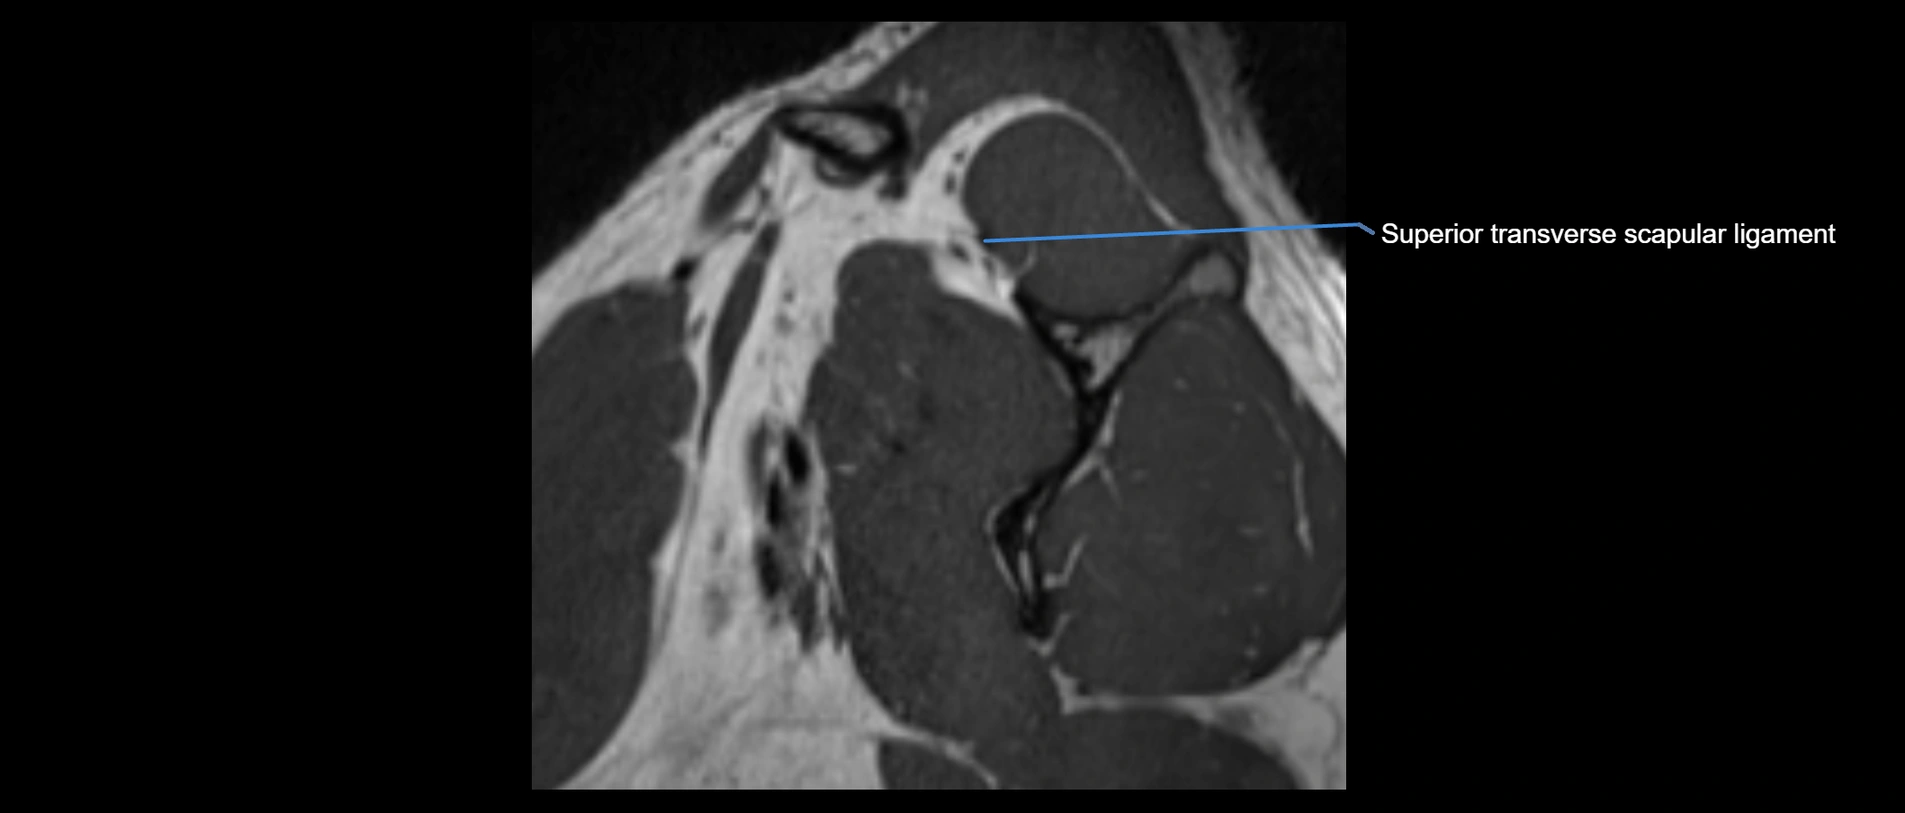

MRI images

image

MRI Appearance

• T1-weighted images:

• Normal ligament: Low signal (dark linear band) spanning acromion to clavicle.

• Surrounding fat planes: Bright, delineating the ligament clearly.

• Marrow of clavicle and acromion: Bright due to fatty content.

• Tears: Discontinuity or irregular thickening with intermediate-to-bright signal.

• Chronic injury: Thinning, fraying, or irregular low-signal fibers with adjacent scarring.

• T2-weighted images:

• Normal ligament: Low signal, homogeneous.

• Partial tear or sprain: Focal hyperintensity or thickening.

• Complete tear: Discontinuity with fluid-bright gap between clavicle and acromion.

• Associated edema: Bright signal in distal clavicle or acromion marrow.